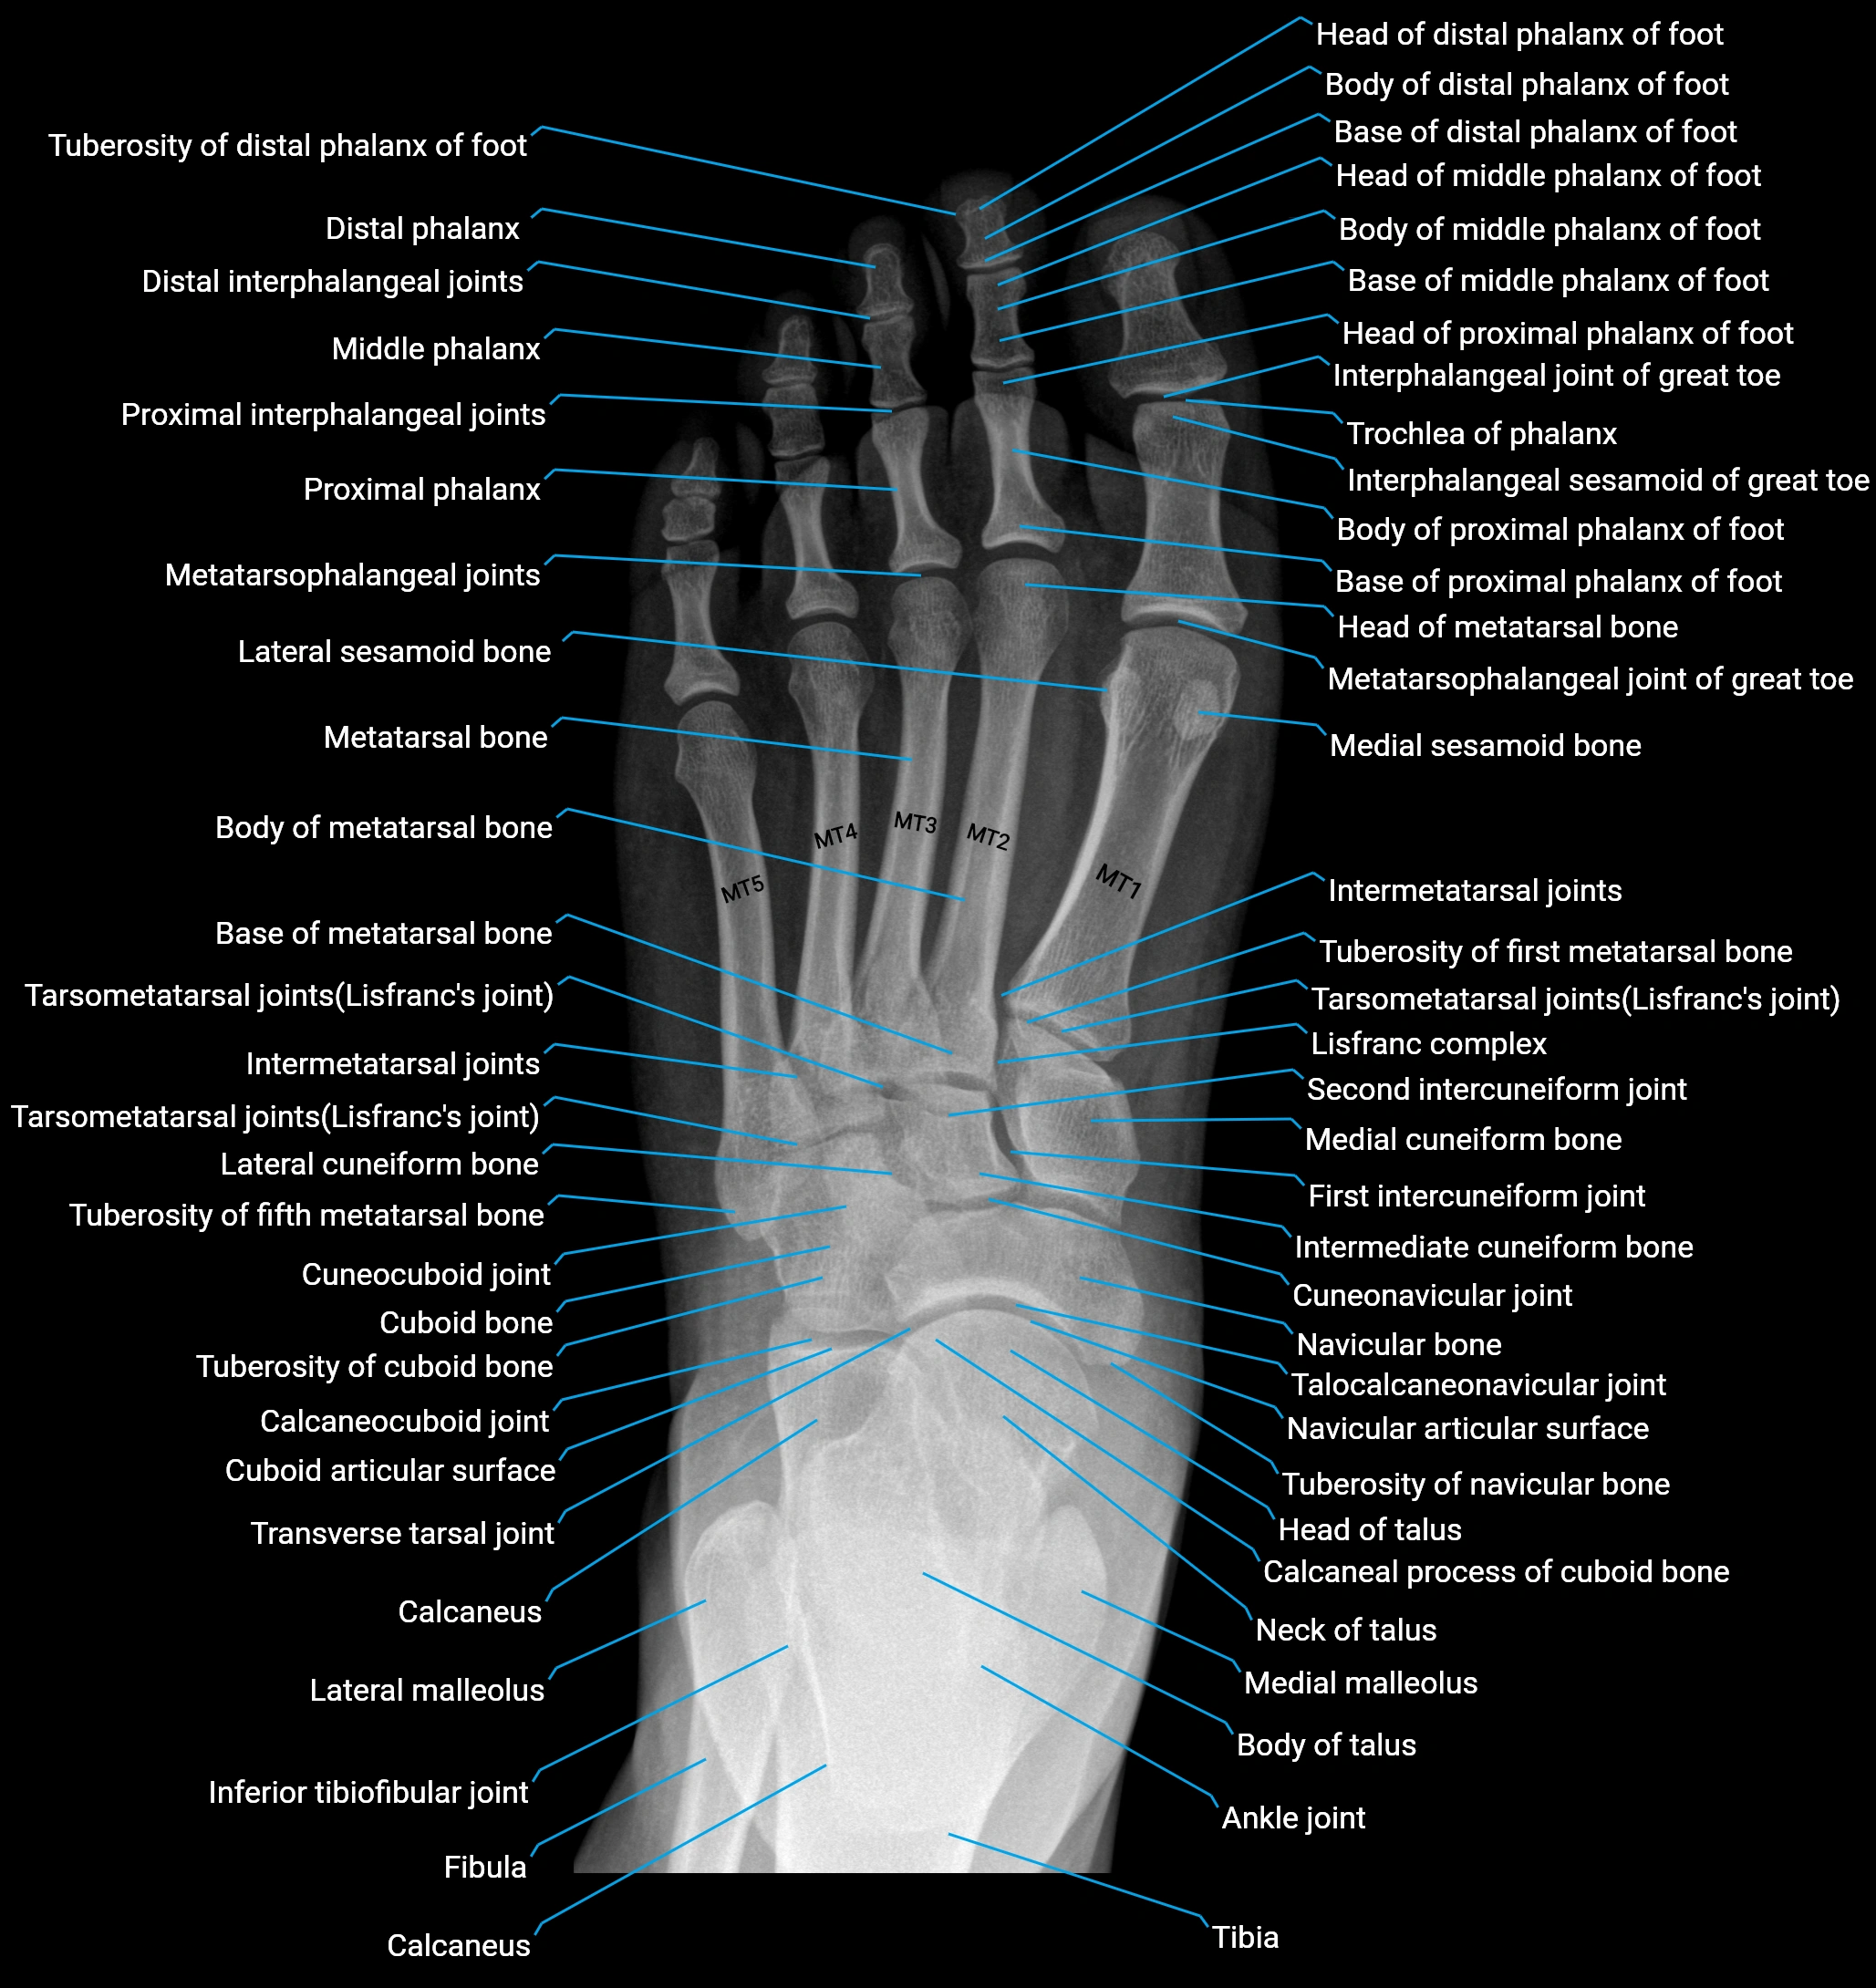

- Ankle joint

- Calcaneus

- Fibula

- Inferior tibiofibular joint

- Intermetatarsal joints

- Interphalangeal joint of great toe

- Interphalangeal sesamoid of great toe

- Lateral malleolus

- Lateral process of calcaneal tuberosity

- Lateral sesamoid bone

- Lisfranc complex

- Medial cuneiform bone

- Medial malleolus

- Medial sesamoid bone

- Metatarsal Bones (MT)

- Metatarsophalangeal joint of great toe

- Metatarsophalangeal joints

- Navicular bone

- Neck of talus

- Second intercuneiform joint

- Talocalcaneonavicular joint

- Tarsal sinus

- Tarsometatarsal joints

- Tibia

- Transverse tarsal joint

- Trochlea of talus

- Tuberosity of fifth metatarsal bone

- Tuberosity of first metatarsal bone

- Tuberosity of navicular bone